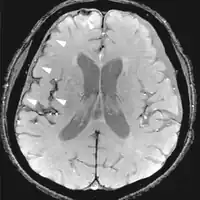

| Fluid-attenuated inversion recovery | FLAIR | Fluid suppression by setting an inversion time that nulls fluids | High signal in lacunar infarction, multiple sclerosis (MS) plaques, subarachnoid haemorrhage and meningitis (pictured).[76] | ![]() | |